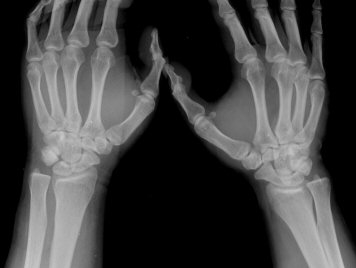

º´·Â

±³Åë »ç°í ÈÄ Å¸º´¿ø¿¡¼­ ¿¢½º·¹ÀÌ Âû¿µÇÏ°í ¿°Á Áø´ÜÇÏ¿¡ Àü¿øµÊ. 3ÁÖ ÈÄ ÅëÁõÀÌ °è¼ÓµÇ¾î ÃÊÁø º´¿ø¿¡¼­ Áֻ縦 ¸Â¾ÒÀ¸³ª Áõ»ó È£Àü ¾ø¾î ´Ù½Ã ³»¿ø

ÀÌÇÐÀû °Ë»ç

¼Õ¸ñÀÇ °üÀý °¡µ¿ ¹üÀ§°¡ °æ¹ÌÇÏ°Ô Á¦Çѵǰí ÁÖ»ó°ñ ºÎÀ§ ¾ÐÅëÀ» º¸ÀÓ